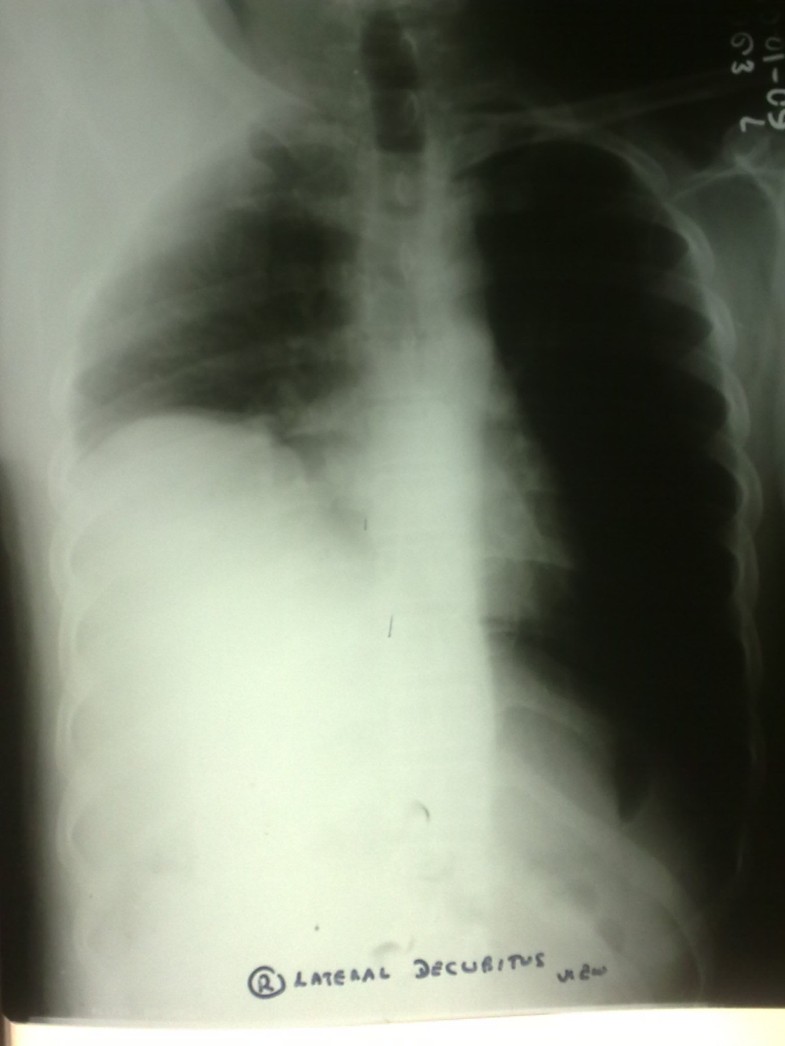

Dengue Hemorrhage Fever With Pulmonary Effusion Stock Photo Download Image Now Anatomy, Bone Chest X Ray For Dengue Chest radiographs showed normal findings in 9 out of the 21 patients. Severe dengue fever is characterized by marked thrombocytopenia, severe hemorrhage, plasma leakage leading to. The most frequently used imaging methods in dengue are chest radiography and abdominal ultrasound, especially in emergency. Diffuse alveolar hemorrhage (dah), commonly defined as the association of hemoptysis, new pulmonary infiltrates on chest. Chest X Ray For Dengue.

Pleural effusion A six years old boy with Dengue shock syndrome. The... Download Scientific Chest X Ray For Dengue The most frequently used imaging methods in dengue are chest radiography and abdominal ultrasound, especially in emergency. Severe dengue fever is characterized by marked thrombocytopenia, severe hemorrhage, plasma leakage leading to. Diffuse alveolar hemorrhage (dah), commonly defined as the association of hemoptysis, new pulmonary infiltrates on chest. Chest radiographs showed normal findings in 9 out of the 21 patients. Chest X Ray For Dengue.